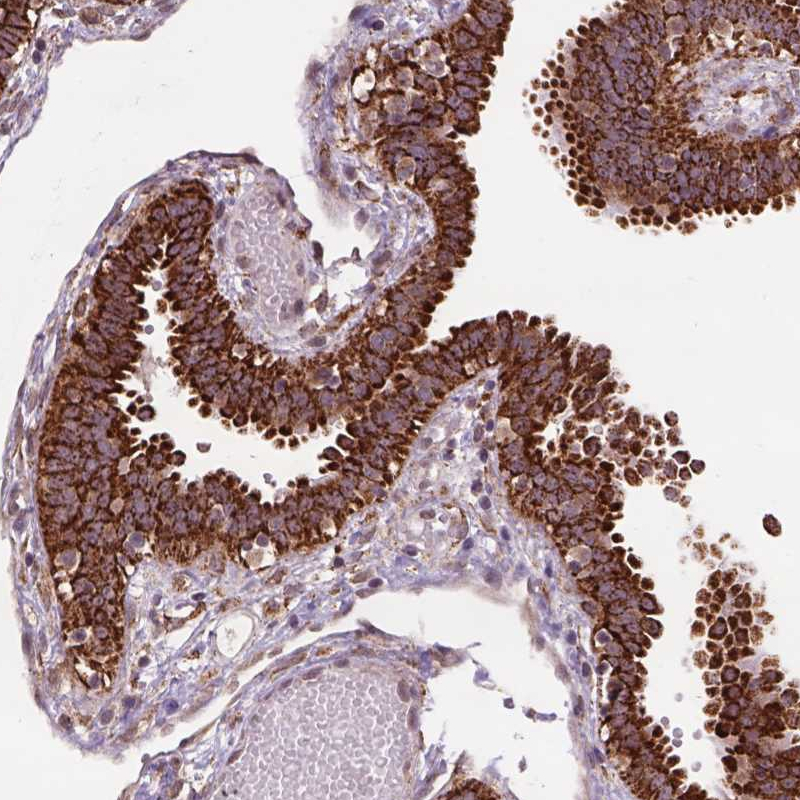

Immunohistochemical staining of human fallopian tube shows strong cytoplasmic positivity in glandular cells.